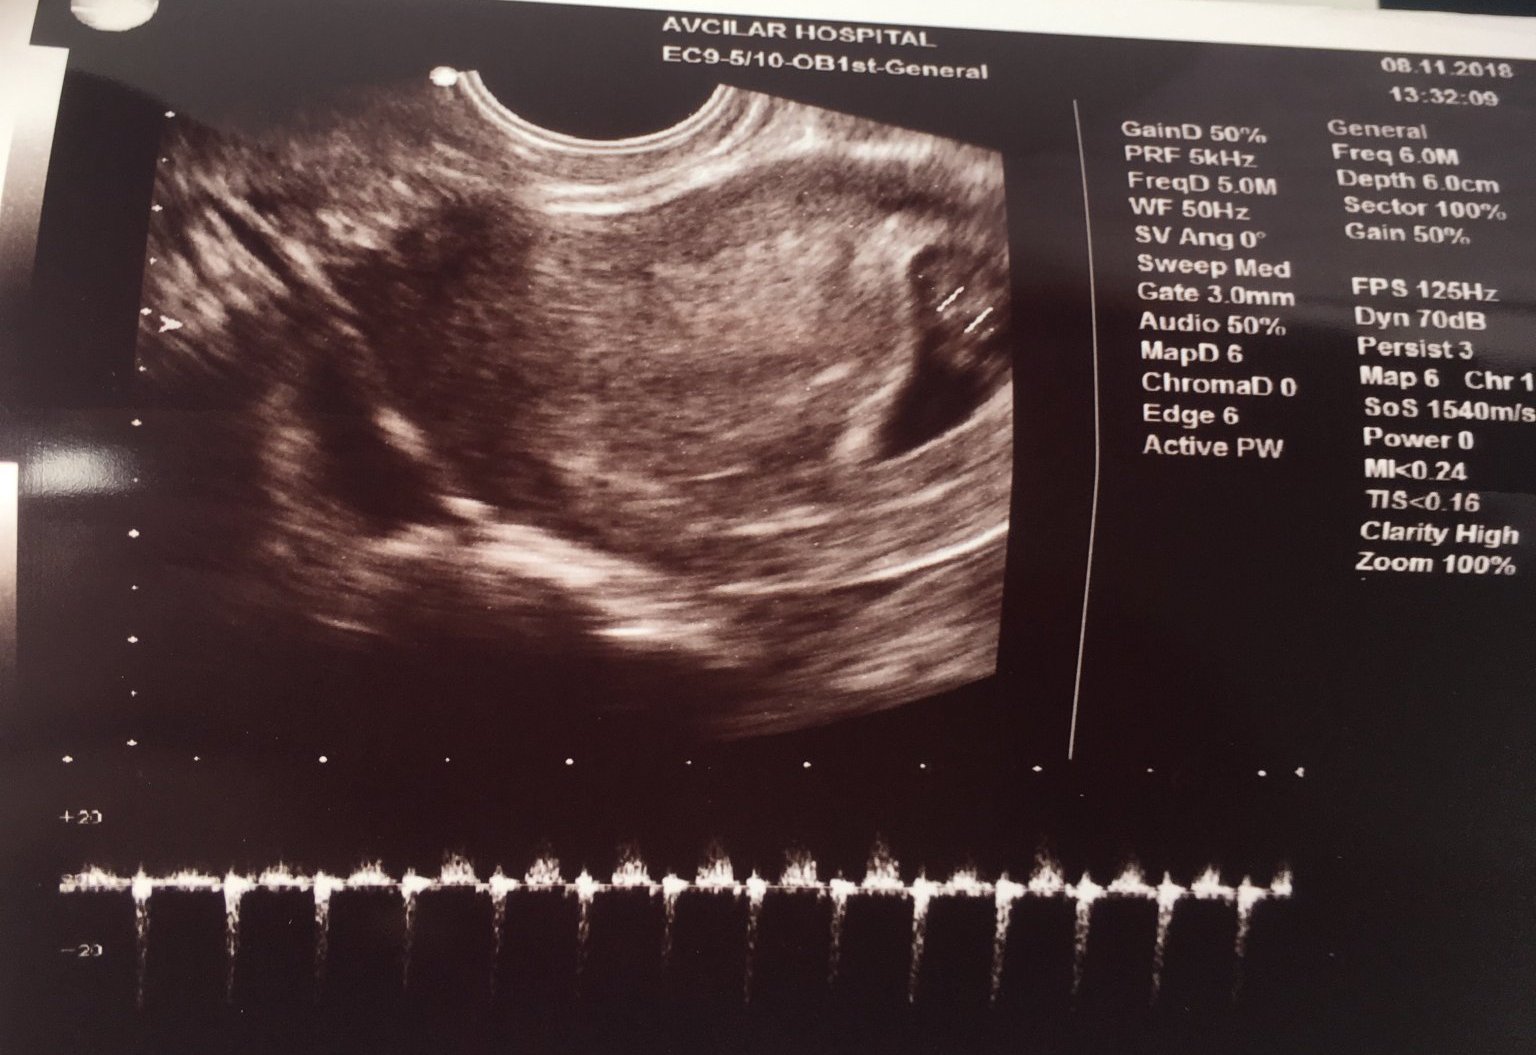

И аз туку що чух сърчице, 7+1 седмица

• Мнения: 2 796

Здравейте, моето „кухо яйце” за сега не е кухо, или поне така казва новият лекар при когото ходя. Само, че по последна м. съм в 8ма седмица, а на ехографа вчера се показа 6сед. и 5 дни. Сакчето е 14,9мм , което не знам дали е нормално и има една мъничка точица..

Но ме притесняват две неща все още не сме видяли сърдечна дейност, не можела да се улови толкова рано, чак след 2 седмици. И също така от два дни имам кафеникаво течение, като снощи се появи и кръв с малки съсиреци и днес отново е кафеникаво .. Лекаря каза, че всичко е наред и да си пия дуфастона и ношпато, но според но не е наред ..

Здравейте момичета! Вчера бях на преглед имам две ембриончета отговарящи на 7 седмица  и 3 дена със сърдечна дейност, но в едното плодно  сакче доктора видя течност и каза, че най-вероятно няма да го бъде.  Чуствам се много объркана.

Привет момичета, да се запиша и аз в темичката, втора бременност, термин 30.06.2019. Днес сутринта бях на преглед, в 6 г.с. , каза ми след 2 седмици да отида за тонове Simple Smile леко бременеене на всички Simple Smile